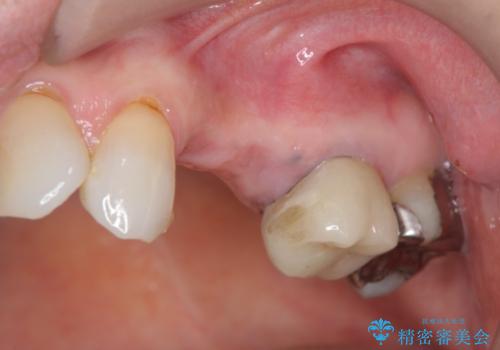

- グラグラする小臼歯の治療、全体的な治療のやりかえを希望され来院されました。

歯の穿孔(内部穴が開いている状態)破折等、歯を保存することができない問題が小臼歯には認められたので抜去を行います。